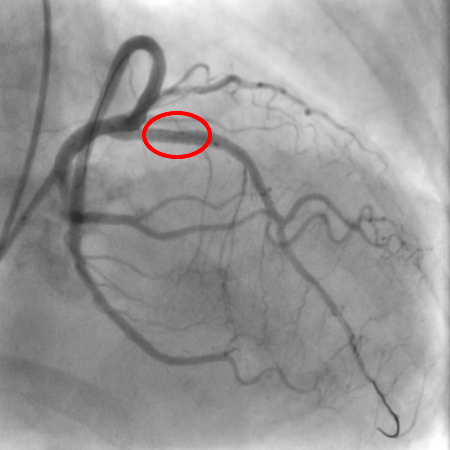

血管撮影とは

血管撮影装置では血管造影(アンギオ検査)を行います。 血管造影とは手首や足の付け根の動脈からカテーテルと呼ばれる細い管を血管の中へ挿入し、目的の位置(血管)まで移動させて血管を造影し、治療を行う検査のことです。

検査内容

主に循環器領域の冠動脈形成術(PCI)、冠動脈造影検査(CAG)、ペースメーカ植え込み術などが行われています。

また外科領域の肝動脈化学塞栓術(TACE)も行っています。PCIとは狭窄した血管や閉塞した血管を、バルーンカテーテルやステントと呼ばれる道具を用いて、血流を回復させる治療法です。

治療前 治療後